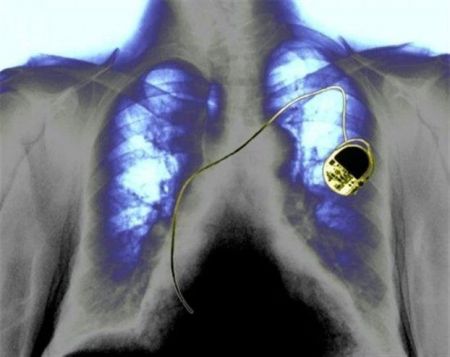

Όσοι έχουν τοποθετήσει βηματοδότη ή εμφυτεύσιμο απινιδωτή στην καρδιά τους, πρέπει να φροντίζουν να διατηρούν σε απόσταση ασφαλείας το «έξυπνο» κινητό τους, κρατώντας το στο αντίθετο αυτί και προσέχοντας να μην φυλάνε το κινητό στην τσέπη τους πάνω από την καρδιά, σύμφωνα με μια νέα γερμανική επιστημονική έρευνα. Μια δεύτερη καναδική μελέτη προειδοποιεί τους κατόχους βηματοδότη ή απινιδωτή να αποφεύγουν να στέκονται κάτω από καλώδια ηλεκτρικού που μεταφέρουν ρεύμα υψηλής ισχύος.